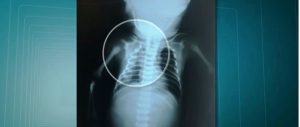

O tiro que atingiu a grávida entrou pelo lado esquerdo de seu quadril. A bala perfurou seu útero e atravessou o corpo de Arthur. Feriu sua cabeça, dilacerou sua orelha, atingiu seu tórax e atravessou sua coluna.